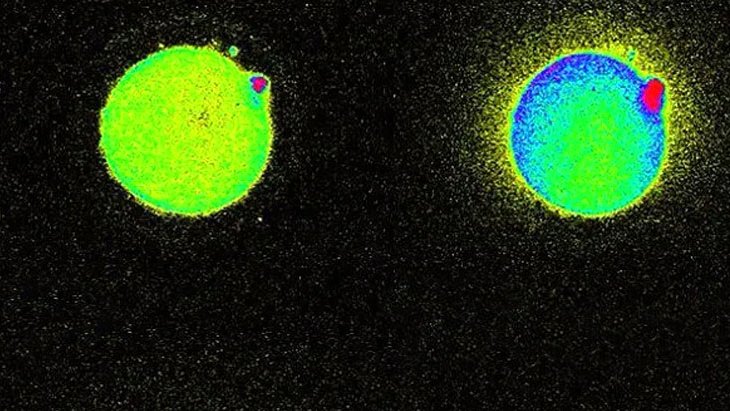

Mucizevi olay daha önce hayvanlarda gözlemlenmişti. Ancak bugüne kadar insanlardaki bu parıltıyı gözlemleyebilen olmamıştı. Bir şaşırtıcı şey ise bazı yumurtalar diğerlerinden daha fazla parlak parlıyor, bu da sağlıklı bir embriyo oluşturabilme konusundaki yeteneklerini gösteriyor.

2011 YILINDA DA GÖZLEMLENMİŞTİ

Bunun öncesinde 2011 yılında yine aynı Northwestern Üniversitesi bilim adamları farelerde sperm yumurtayla birleştiğinde oluşan çinko parıltılarını gözlemlemişti.

KANITLAMAK İÇİN UZUN YILLAR BEKLEDİLER

Bu olayı nasıl kanıtlayacaklarını yıllarca düşünen bilim insanları 2014 yılında bu olayı ilk defa gözlemlemiş, ve sperm yumurtayı deldiği anda salgılanan serbest duruma geçen milyarlarca çinko atomunu seyretmişti.

FLÖRASAN ALGILAYICI İLE GÖRÜNTÜLEDİLER

Yeni bir flörasan algılayıcı kullanarak canlı hücrelerdeki çinko atomu hareketlerini takip eden bilim ekibi, yumurtadaki çinko depolama yeteneğini fark etti. Yaklaşık 8000 değişik küçük haznede depolanan 1 milyon civarında çinko atomu döllenme gerçekleşince havai fişek gibi ateşleniyor. Döllenmenin ardından 2 saat boyunca bu olay devam ediyor. Kaynak: Süperileri.com, Nature.com